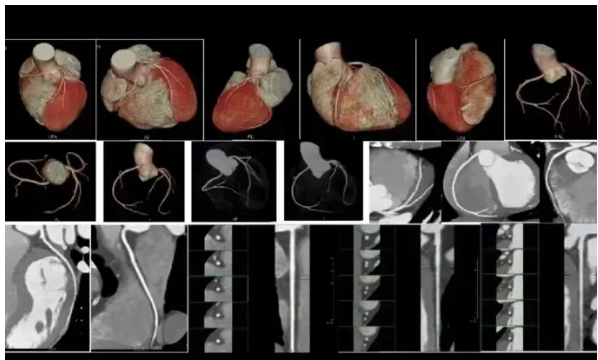

有高血压、高血脂、糖尿病等基础疾病,日常常出现胸闷、胸痛、心慌等症状,或有冠心病家族史的人群,可选择西门子双源CT进行冠脉CTA检查。这款设备扫描速度极快,一次屏气约5 - 6秒就能完成心脏冠脉检查,即便老年体弱、无法长时间憋气的患者也能轻松耐受。它能清晰显示冠脉血管的狭窄程度、斑块情况,精准排查冠心病等心血管疾病风险,实现早发现、早干预。